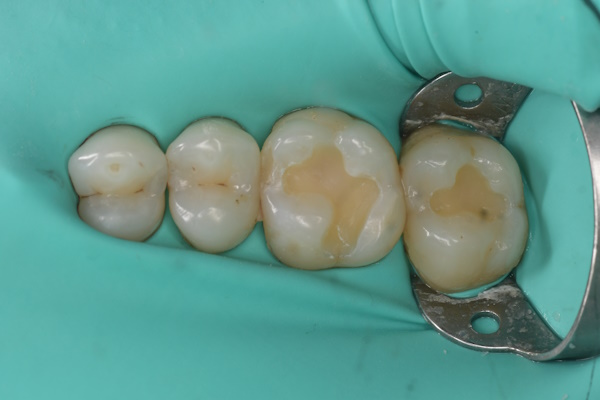

セラミック治療の治療例です。奥歯の虫歯を、見た目もきれいな材料で治したいとのご希望で来院されました。当院にて、2本同時にセラミック治療を行いました。接着効率を高めるため、ラバーダムを使用しています。オキシガードは、過酸化物と還元剤による化学重合反応により、歯科接着用レジンセメント表面の未重合層を硬化させる材料です。さらに、未重合層を空気から遮断することで、確実な硬化を促します。

術前から術後までの治療の流れ

虫歯処置後